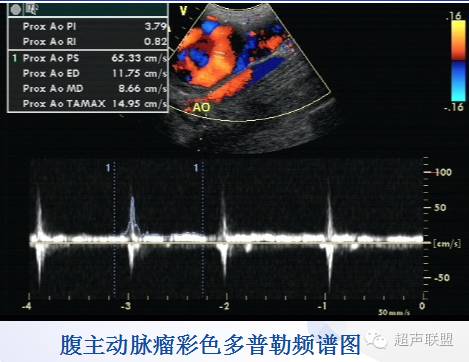

* 真性动脉瘤:当一条动脉病变处的管径为相邻正常管径的1.5倍以上时称真性动脉瘤。

好发部位:腹主动脉、腘动脉、升主动脉、颈动脉。

继发改变:动脉瘤破裂,血栓形成与栓塞;继发感染。

常见病因:动脉粥样硬化,感染,先天性少见。

* 病理与声像图:真性动脉瘤,假性动脉瘤,夹层动脉瘤。

真性动脉瘤 | 假性动脉瘤 | |

病因 | 动脉硬化、感染致主动脉瘤样扩张 | 多为外伤致动脉管壁破裂、感染、医源性 |

肿块部位与形态 | 沿动脉纵向分布,呈梭形、囊状、圆柱状 | 位于动脉的一侧或前后,呈囊性或不规则 |

瘤壁结构 | 可分辨动脉管壁三层结构,常有钙化斑块 | 无动脉管壁三层结构,常无钙化斑块 |

瘤壁破裂口 | 无 | 有 |

进口与出口 | 进口与出口分开 | 同一通道 |

双期双向血流 | 无 | 有,血流从同一瘤口进出 |